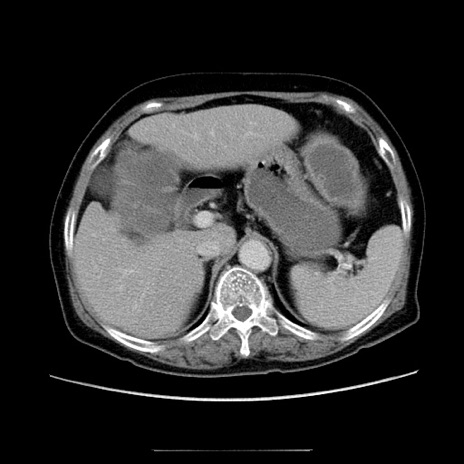

冠状断像

【症例】70歳代女性

【主訴】お腹が張る

【現病歴】1週間くらい前から腹部膨満の自覚あり。昨日夜から増悪したため、本日救急外来受診。

【身体所見】意識清明、BT 36.5℃、BP 165/106mmHg、HR 80bpm、SpO2 98%、腹部:膨満、軟、自発痛・圧痛なし、触診にて不快感あり、腸蠕動音:減弱

【データ】WBC 12600、CRP 1.04